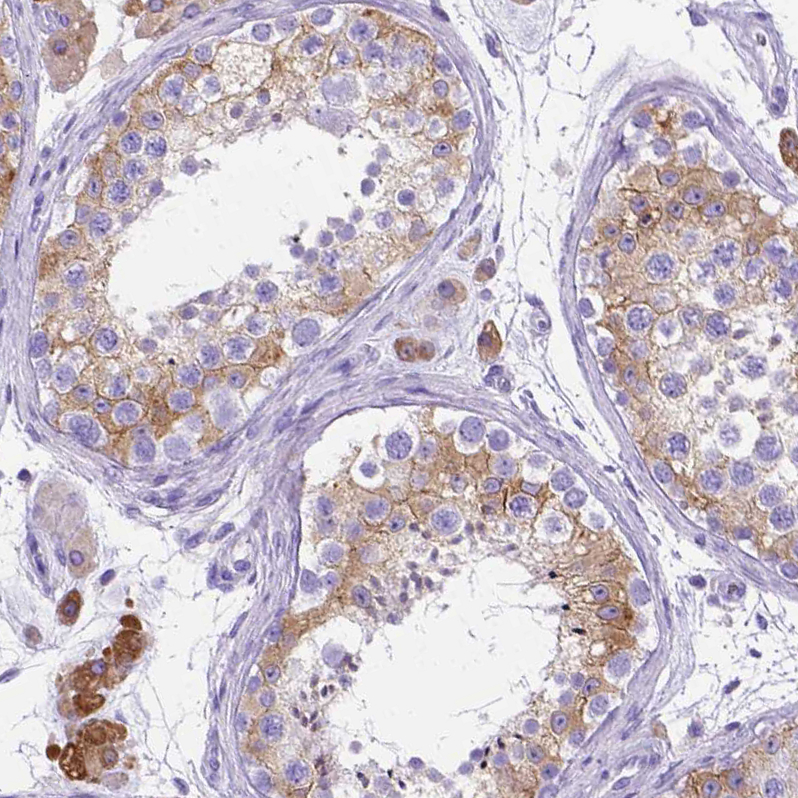

Immunohistochemistry analysis in human seminal vesicle and pancreas tissues using HPA045064 antibody. Corresponding PTGES RNA-seq data are presented for the same tissues.